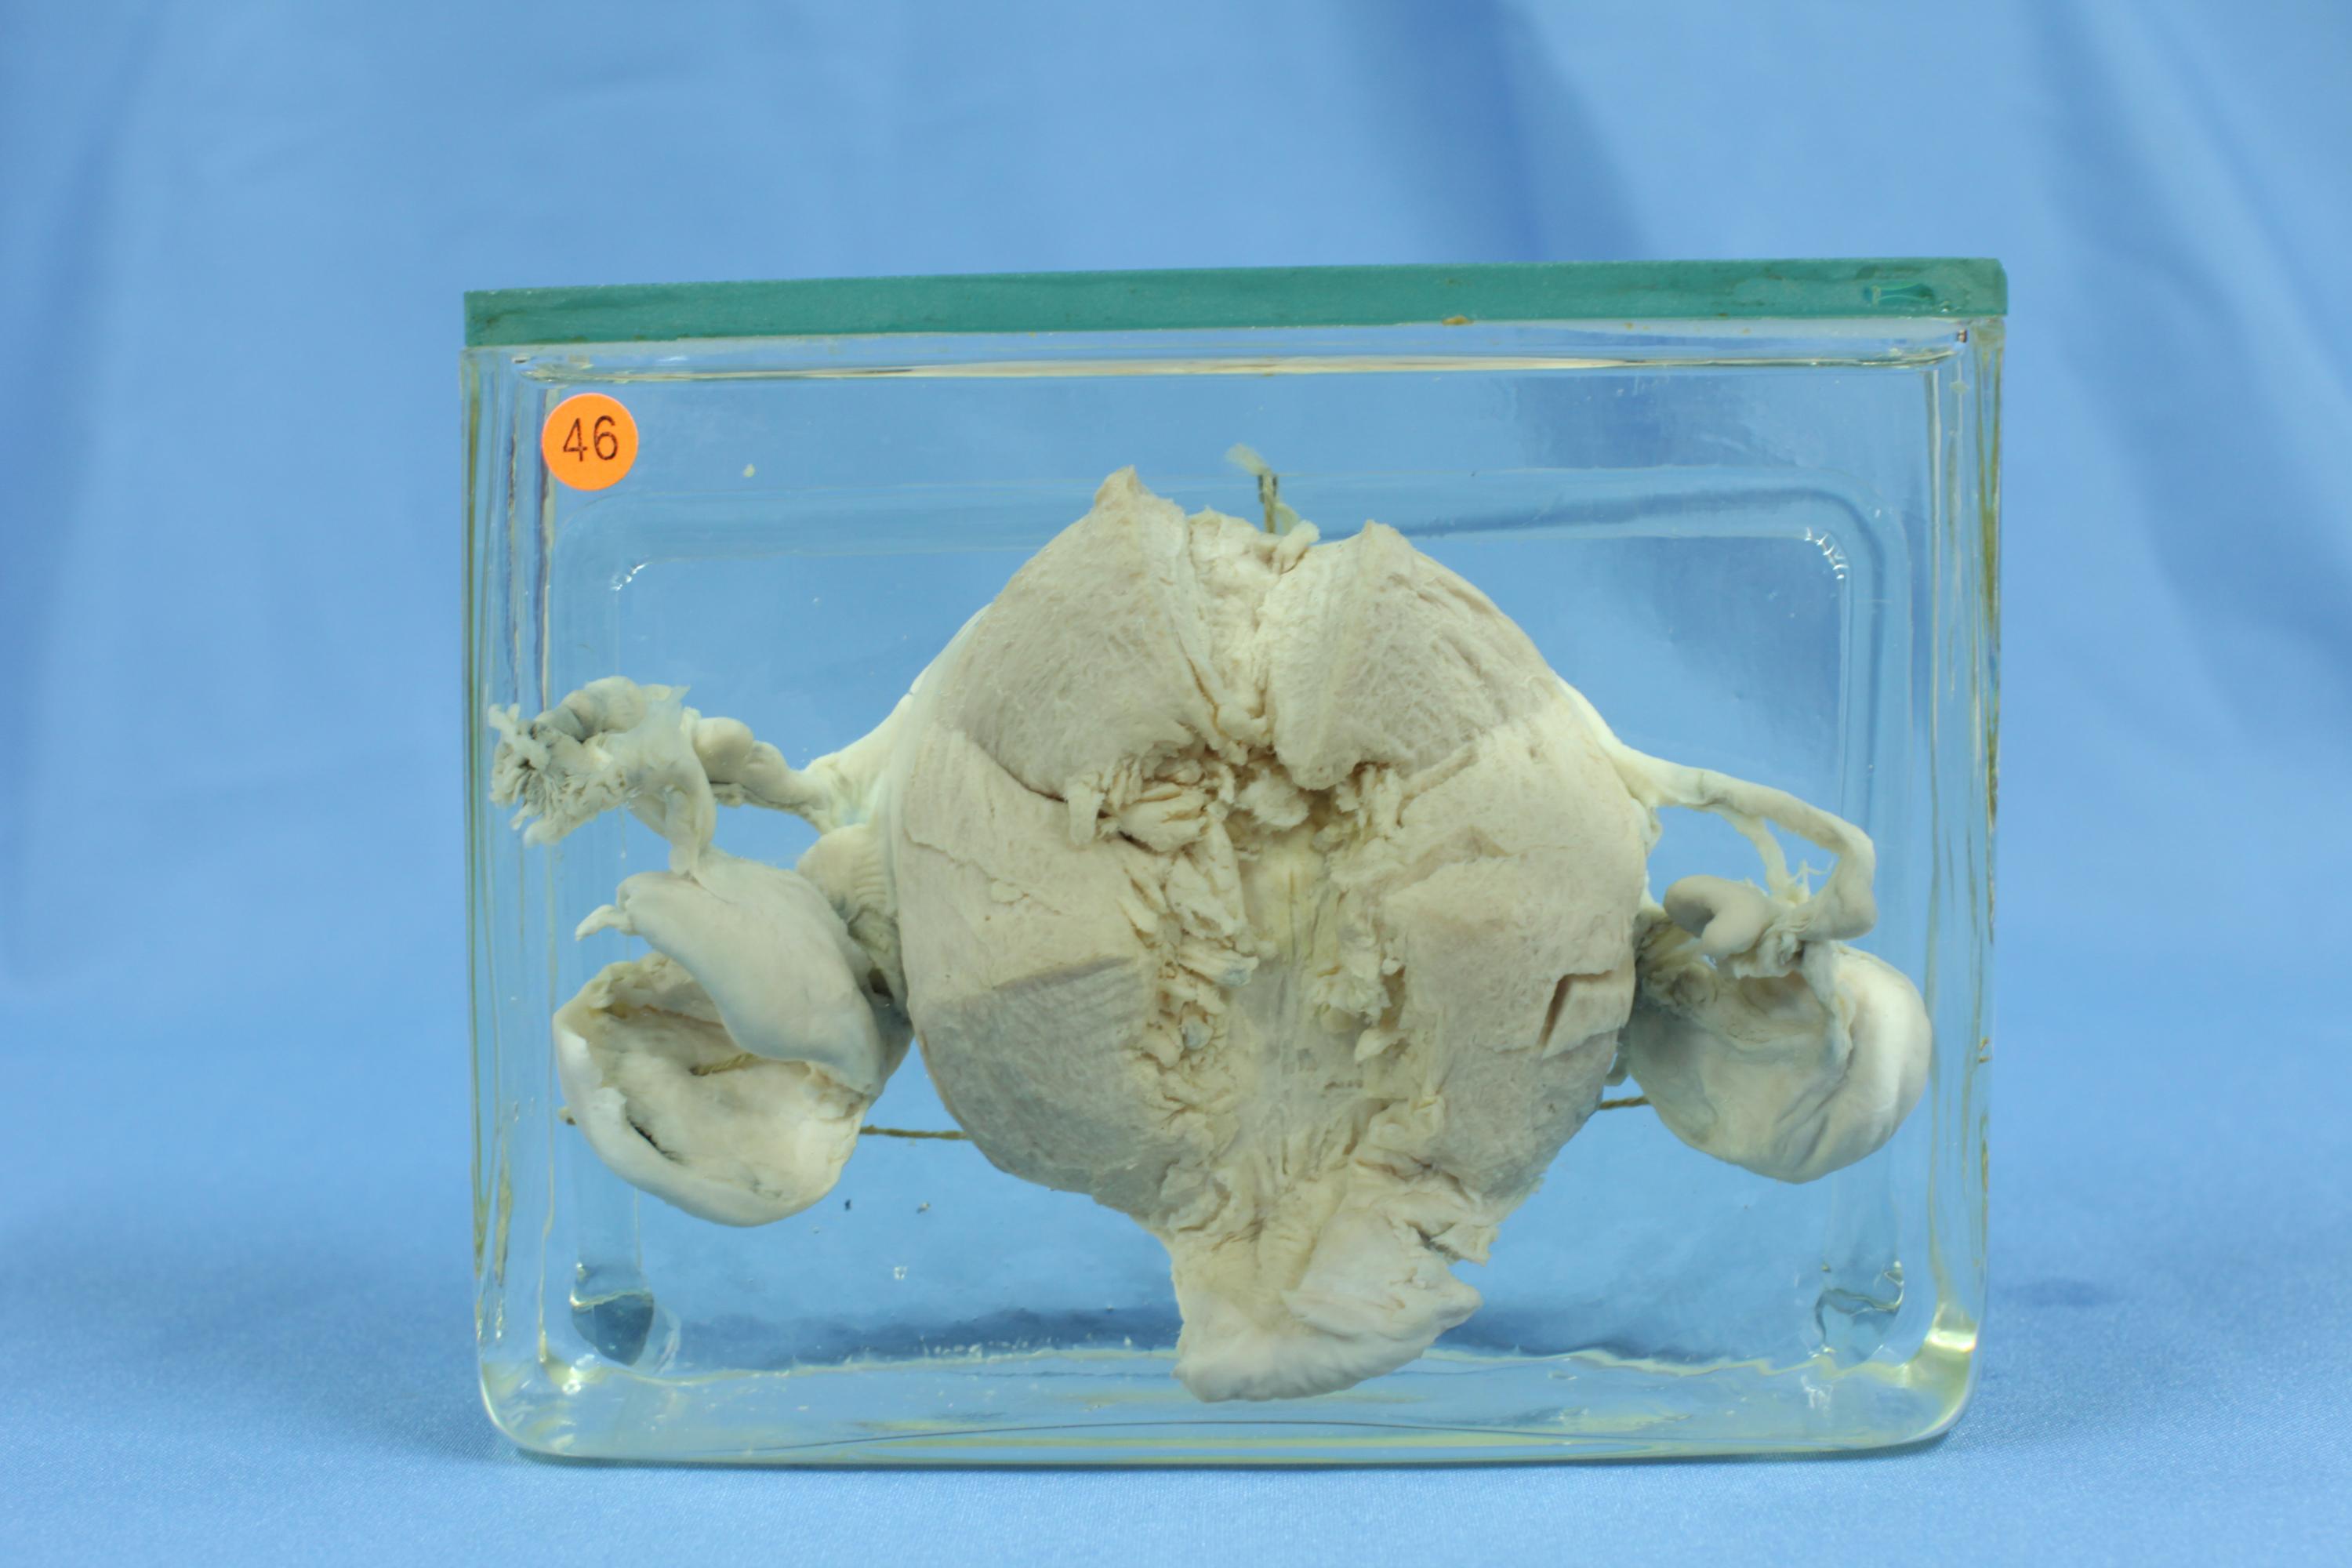

生殖疾病43-46. 子宫内膜增生过长 (息肉型)(55-5489)

中央为切开子宫,子宫内膜呈息肉样弥漫增生并向子宫腔内突起。两侧卵巢均有囊肿形成。